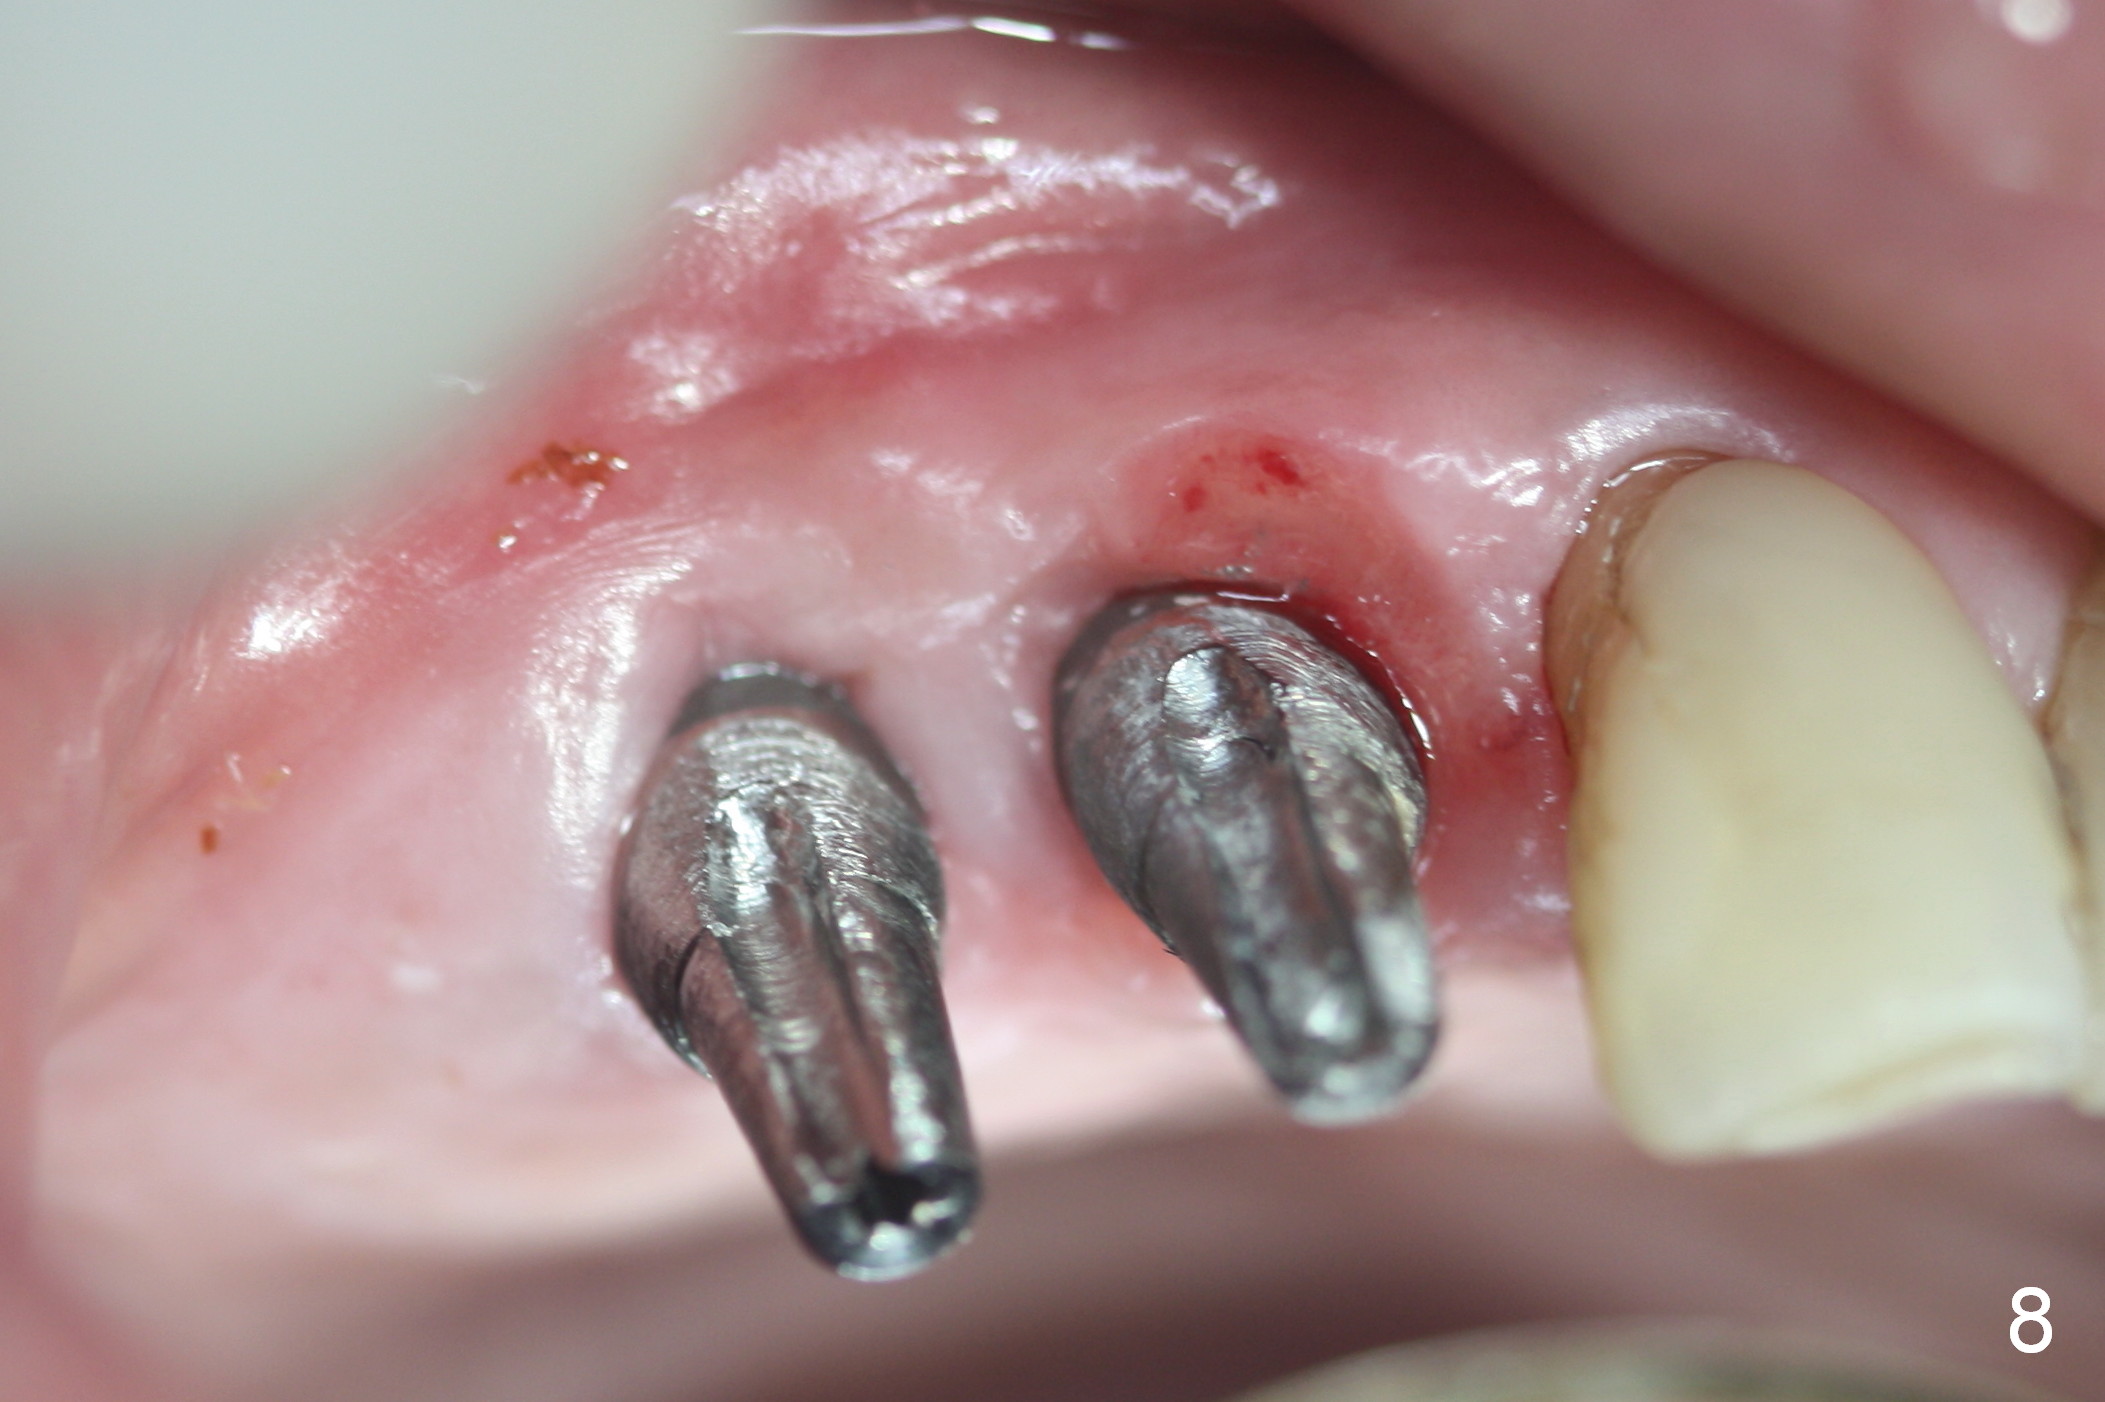

Several of CK's upper teeth (apparently in cross bite) are to be restored with implants (Fig.1). The first two are #5 and 6; note the oval roots (Fig.2). After extraction, and curettage, osteotomy starts in the palatal aspect of each socket. The 1st intraop PA shows that the trajectory at #6 is incorrect (Fig.3). After adjustment, osteotomies look parallel (Fig.4: D: 3.5x20 mm drill; T: 4.5x20 mm tap). This suggests how important it is to use parallel pins to check initial osteotomies for neighboring implants (Fig.3). The trajectory of the implants remains acceptable (Fig.5: 4.5x20 mm with insertion torque »60 Ncm); so is the position of the implants (as palatal as possible; Fig.6 (*: bone graft)). Immediate provisionals are fabricated in cross bite.

Bone density in the distal gap of #5 appears to have increased 3 months postop (Fig.7). Prior to definitive restoration cementation (3.5 months postop), the buccal plate does not collapse (Fig.8). There is no occlusal contact of the new restorations (Fig.9 *), probably due to bite discrepancy (Fig.10,11).